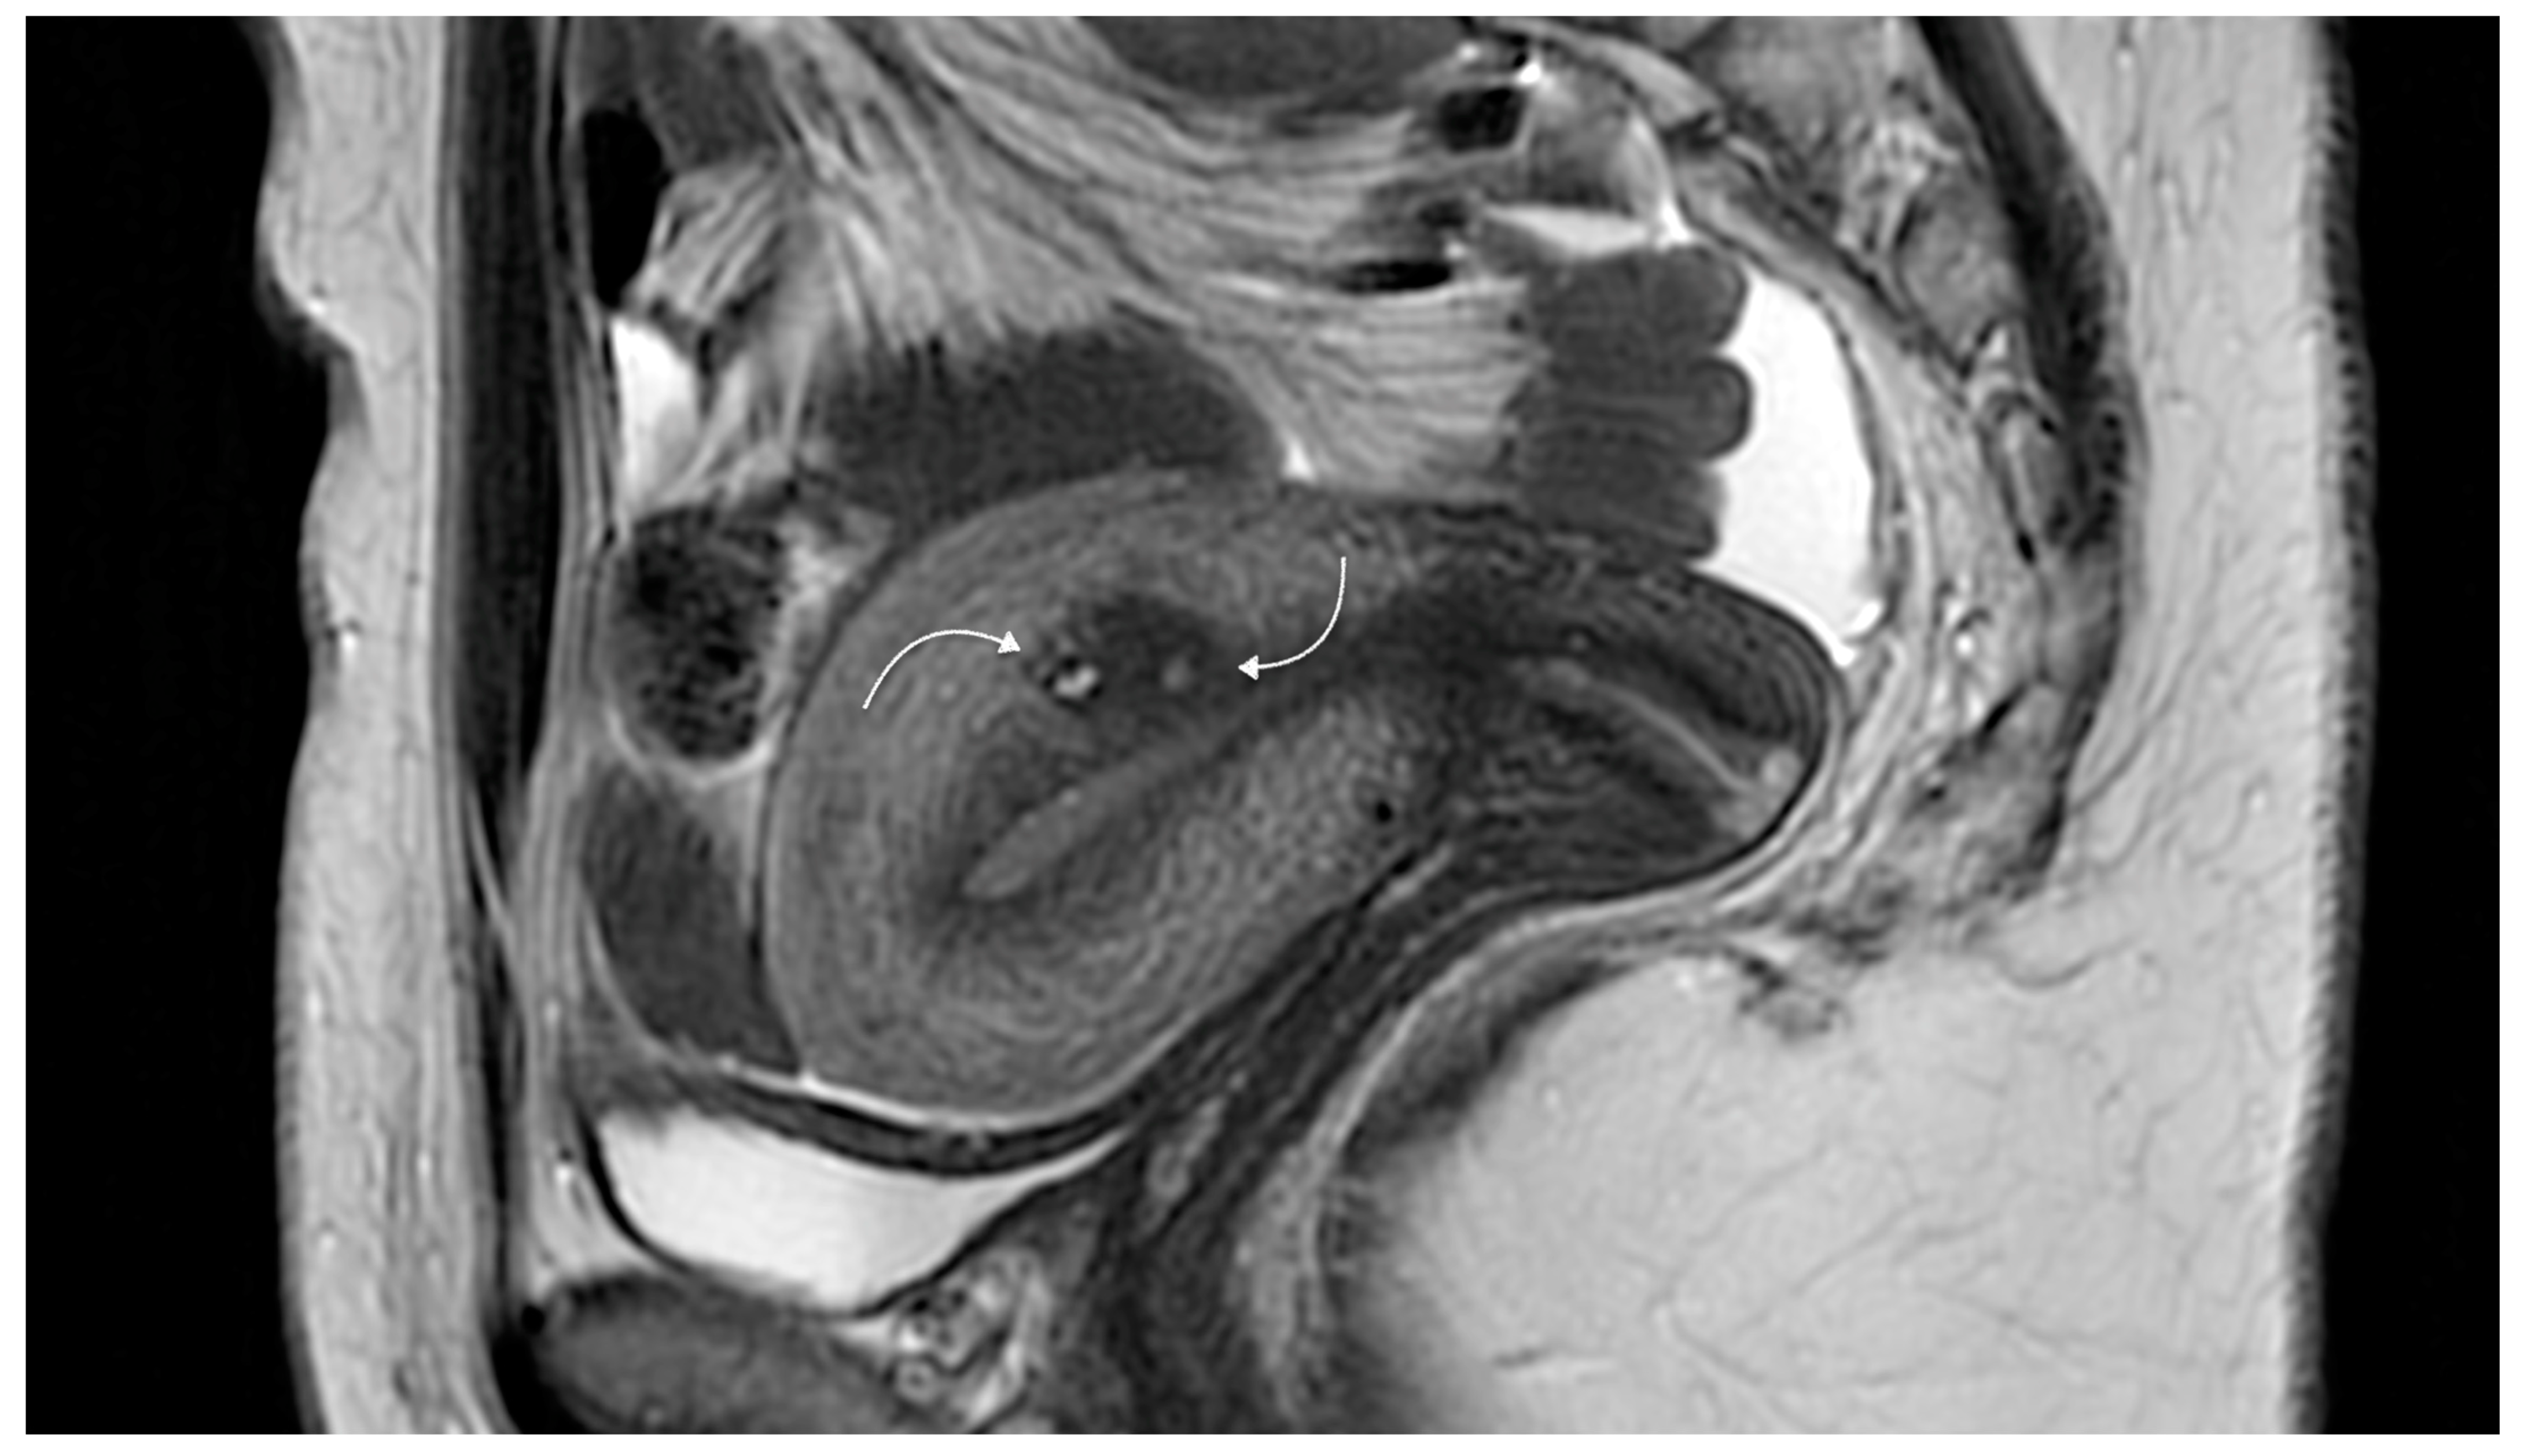

- Magnetic resonance imaging (MRI)